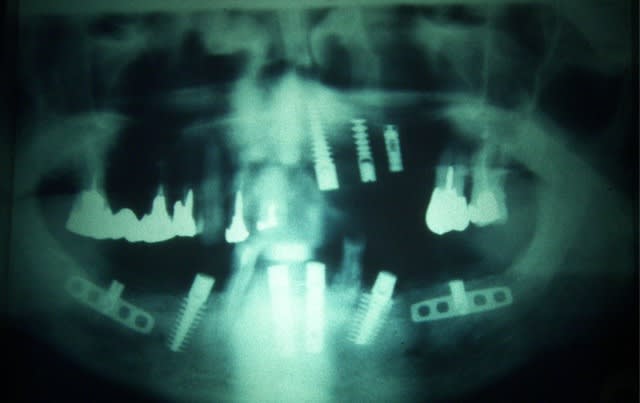

Merci Olivier, dans la série c'est dans les vieux plats que l'on fait la bonne soupe, même si les "jeunes" préfèrent les packs, un autres cas qui montre que les implants ne sont pas tous de simples trucs tout ronds à visser:

Et surtout que la gestion paro prothèse était déjà importante fin 80.

Ce cas à m'a permit de former ma prothésiste, débutante de moins d'un an, à un travail sur implant. (ceramik doucement, le cadcam n'existait pas)

les implants etaient:

haut:D2 Tatum (3.5x5x20mm)

P4 Tatum impacté (4x17)

TBR (lisse...) 13mm je crois

Bas: 2 Lames TBR grand modèle

2 D3 Tatum (3.5x7x20mm dont 1 racourci à la pose)

2 R4 Tatum (4x20mm)

posés en une scéance, au fauteuil!

un peu bourin à l'époque

Pour la ligne verticale ce n'est pas joli en radio mais je fonctionnais déjà fonction de l'os (la belle excuse) exemple le D4 en 33/34 pour être à l'abri du foramen, car poser des impactés comme ceux là au max. inf. ce n'est pas de la tarte.

Le patient est mort (pas des suites de ça...) en 2007 sans avoir jamais eu le moindre souci.